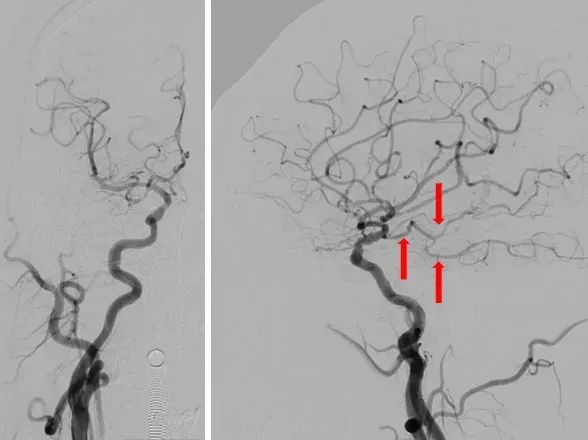

造影示:右侧优势椎,经右侧椎动脉导弯造影,双侧胚胎型大脑后动脉。

术前DSA:双侧后交通动脉开放。

R-CCA

L-CCA

R-VA

L-SUB-VA